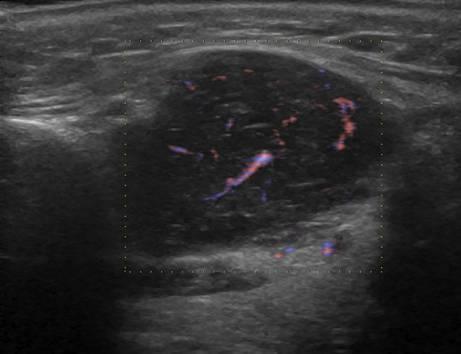

U tuyến nước bọt

» Thông tin: Nam giới – 63 tuổi.

» Lâm sàng: Khối vùng góc hàm.

# Lymphoma tuyến nước bọt dưới hàm.